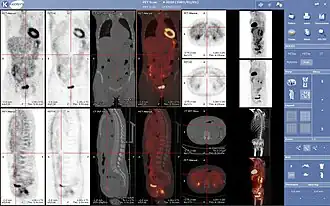

- 3D: ОФЭКТ — это трехмерный томографический метод, который использует данные гамма-камеры из многих проекций и может быть реконструирован в разных плоскостях. ПЭТ использует обнаружение совпадений для отображения функциональных процессов.

ОФЭКТ-сканирование печени ядерной медицины с мечеными технецием-99m аутологичными эритроцитами. Очаг высокого поглощения (стрелка) в печени соответствует гемангиоме. -

Проекция максимальной интенсивности (MIP) позитронно-эмиссионной томографии (ПЭТ) всего тела у женщины весом 79 кг после внутривенной инъекции 371 МБк 18F-FDG (за один час до измерения).

Нормальная ПЭТ/КТ всего тела с ФДГ-18. ПЭТ/КТ всего тела обычно используется для выявления, определения стадии и последующего наблюдения за различными видами рака. -

Аномальная ПЭТ/КТ всего тела с множественными метастазами рака. ПЭТ/КТ всего тела стала важным инструментом в оценке рака.